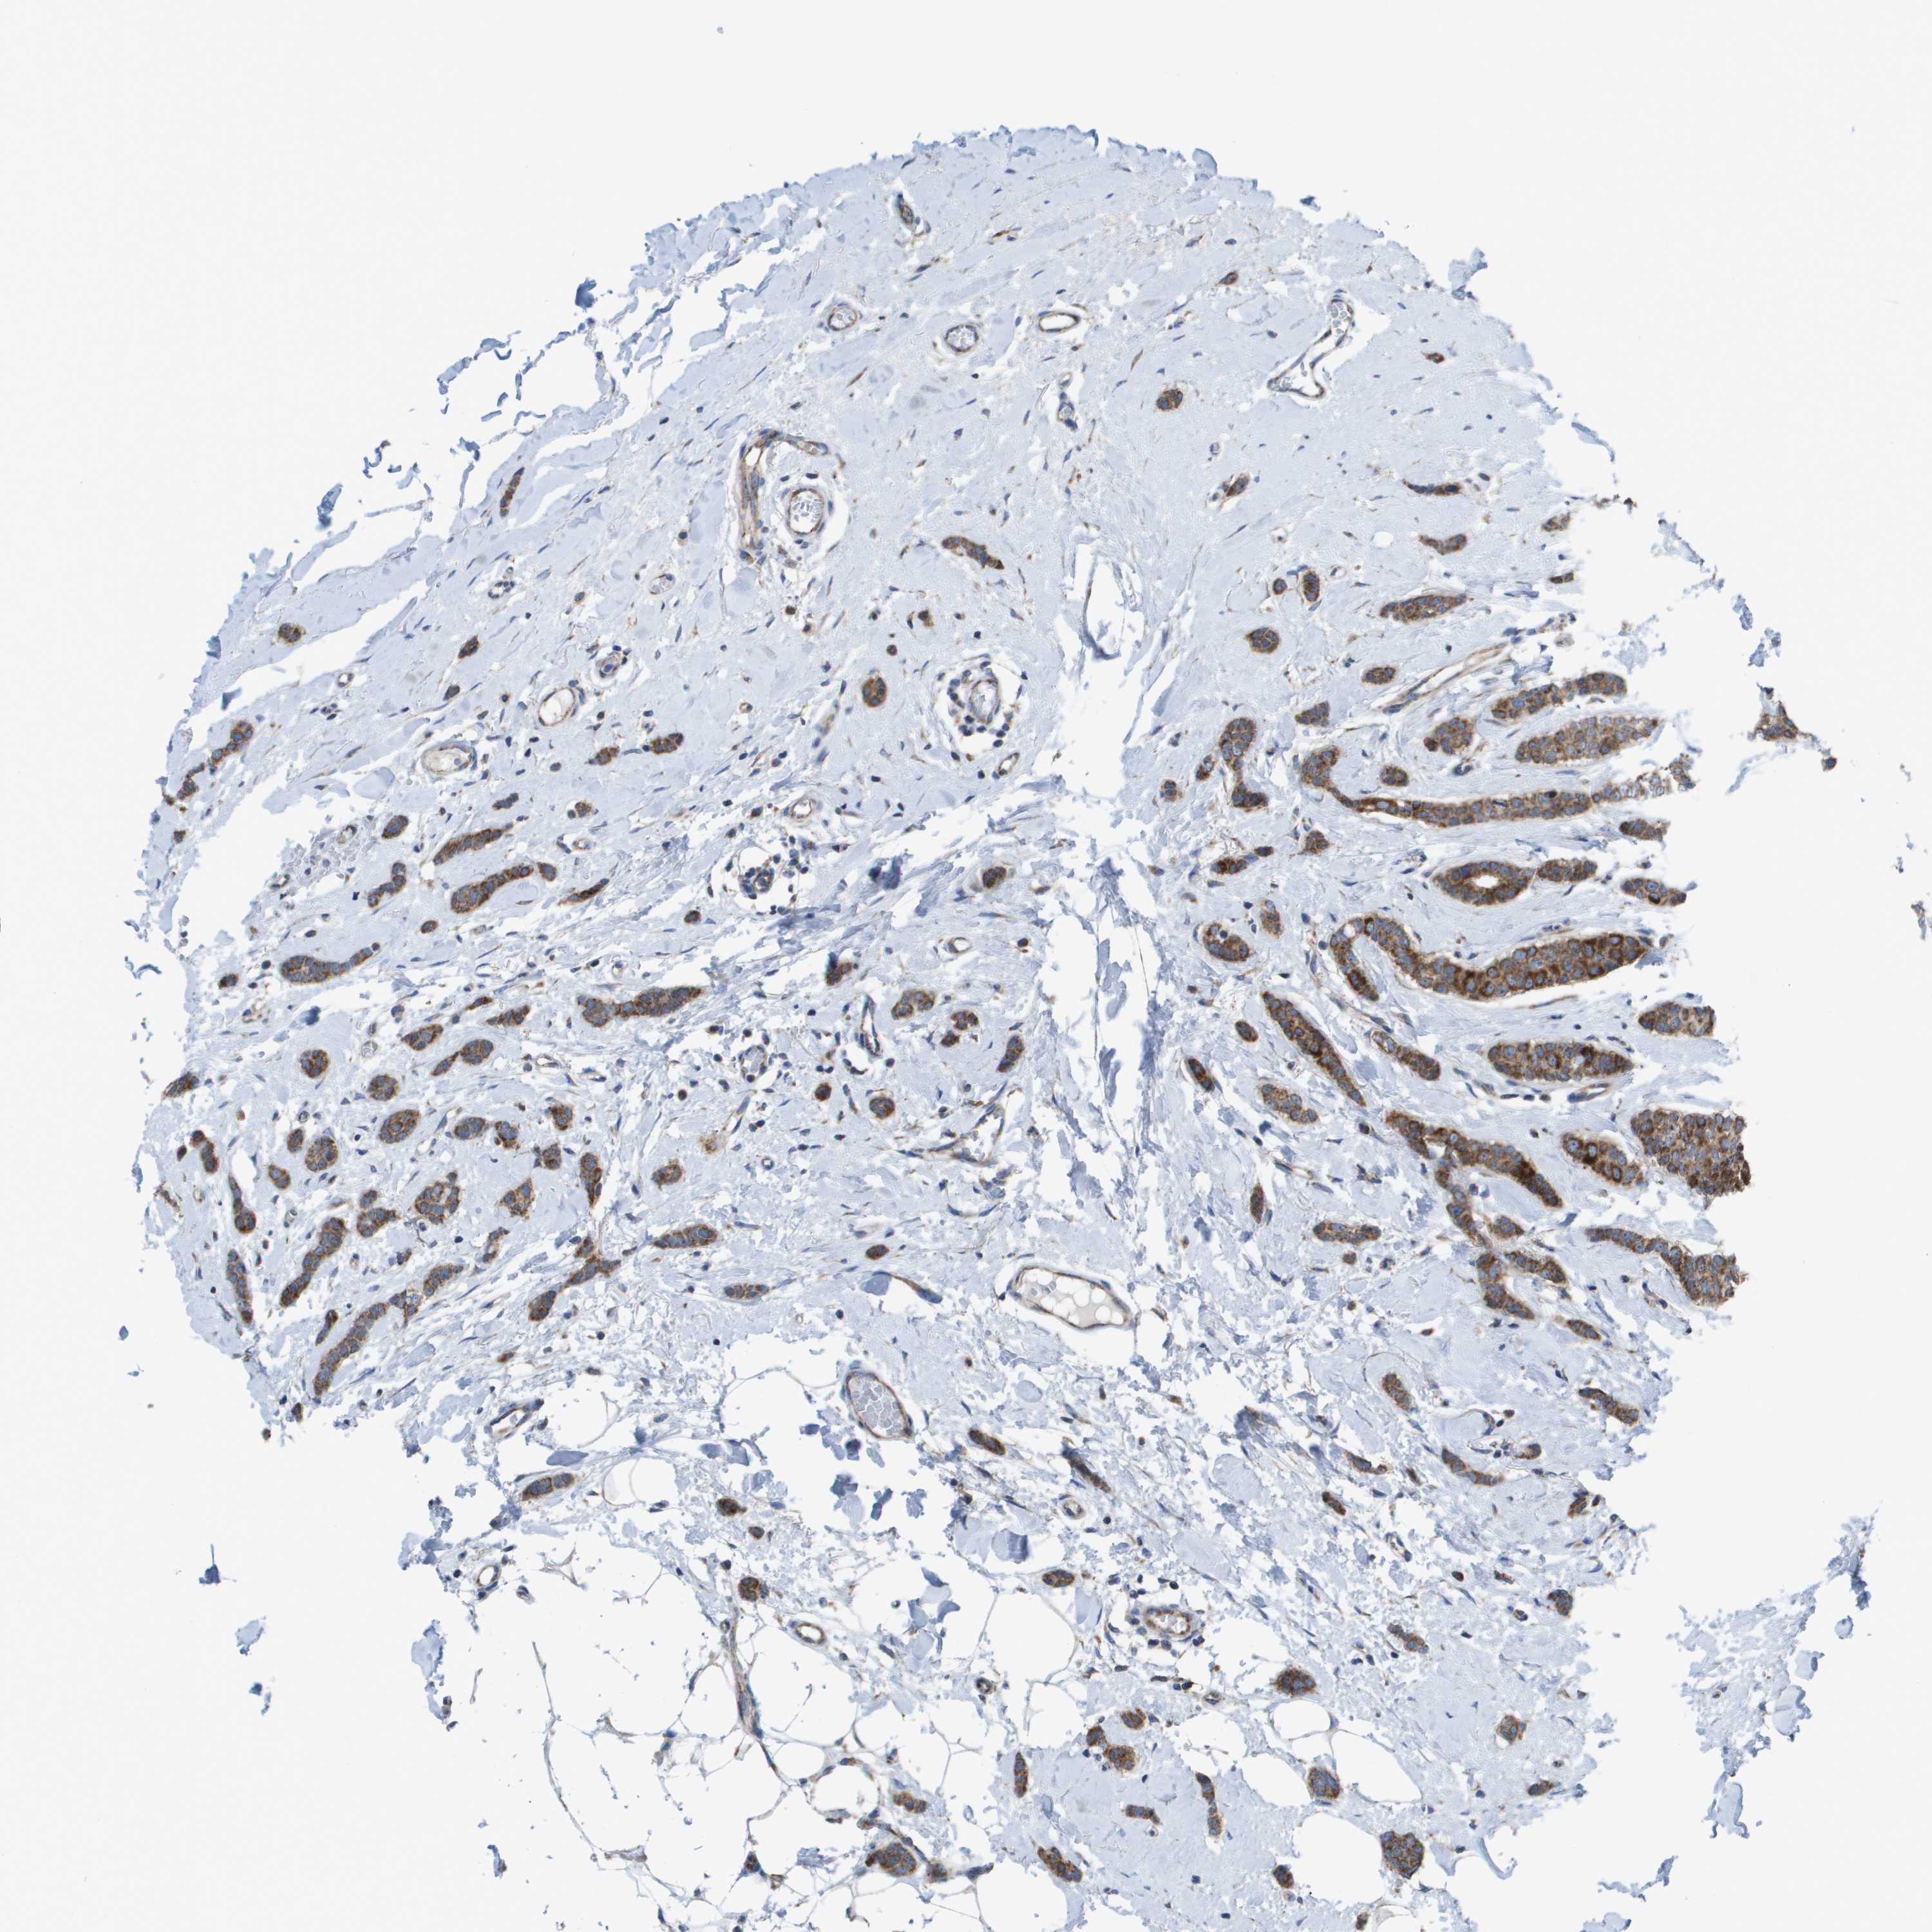

BRCA TCGA BRCA VALIDATION PROTEIN EXPRESSION

ANTIBODIES

AND

VALIDATION